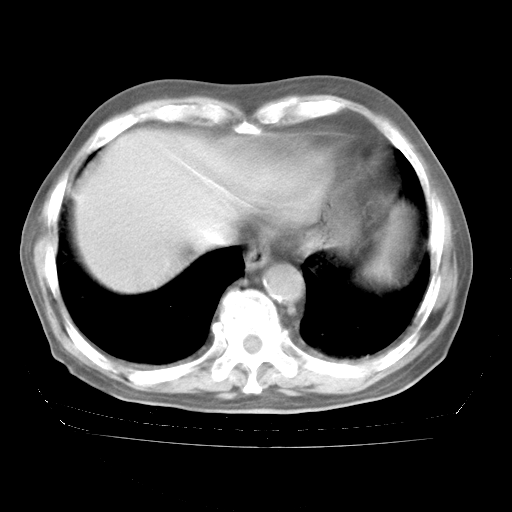

4月28日肺部CT